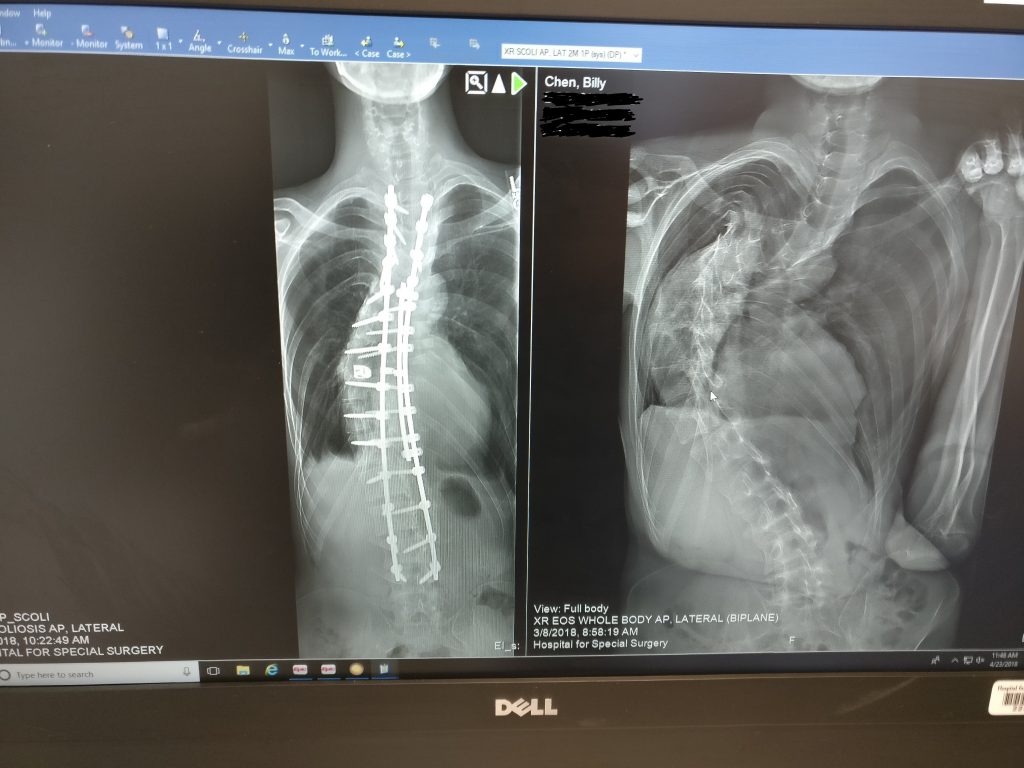

I found out about my scoliosis at the age of 15 when my mother noticed my right shoulder blade was subtly protruding. At the time, my curvature was around 20-30 degrees. We tried every possible non-surgical treatment ranging from physical therapy to wearing a back brace, but nothing worked. As time passed, my curvature was getting worse. At the time, we were not living in the U.S., and each surgeon we visited did not seem confident or competent enough to do the surgery. On top of that, I have Marfan Syndrome, which doctors were not very familiar with but knew would complicate the surgery. Because of this, we decided hold off on any type of surgery.

After I moved to New York for college, my family and I agreed I was in the best place to find a spine surgeon. After seeing a few doctors, I was referred to Dr. Kim. After seeing so many doubtful doctors, it was one of the most relieving experiences having my first appointment with Dr. Kim. Despite my 100+ degree curvature, he was extremely confident that he could perform my surgery. Seeing the extensive research Dr. Kim did in preparation for the surgery assured me that I was in very good hands.

After two months of halo-gravity traction (HGT) pre-surgery, nine hours of spinal fusion surgery, and four months of post-operative recovery, I am now writing this to show my gratitude toward all the doctors, nurses, and office staff at HSS who helped me throughout this process. Even with two more months of post-operative precautions, I am feeling better than I ever had. Just last year, I was convinced I'd have severe scoliosis for the rest of my life. I am forever grateful for what Dr. Kim and his team were able to do for me.